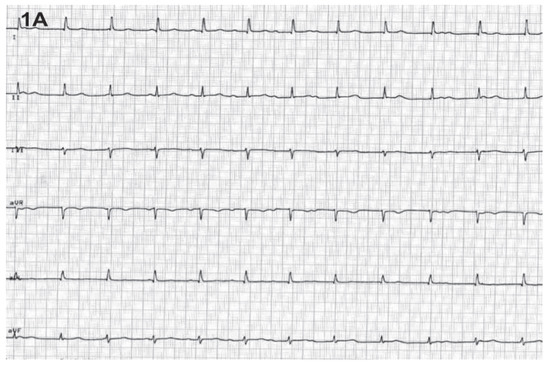

We report on the worldwide first implantation of a transcatheter valve in mitral position using a surgical approach to treat severe combined mitral valve disease, complicated by massive calcifications of the whole mitral anulus. The management of suc...